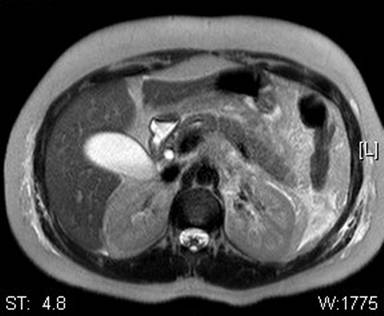

An ultrasound of the right upper quadrant was unremarkable, without evidence of cholelithiasis. Abdominal computed tomography (CT) scan revealed significant inflammatory changes including peripancreatic fluid and fat stranding that extended into the pericolic gutter as well as thickening of the posterior gastric wall, left perinephric stranding, and periportal edema with normal pancreatic anatomy. Magnetic resonance cholangiopancreatography (MRCP) performed two days after admission revealed similar peri-pancreatic inflammatory changes and normal pancreatic anatomy. There was no evidence of gallstone or sphincter dysfunction. The changes discussed above are represented in Figures 1, 2, and 3.

Figure 2. Previous CT changes seen in Figure 1 show T2 enhancement on MRCP. |